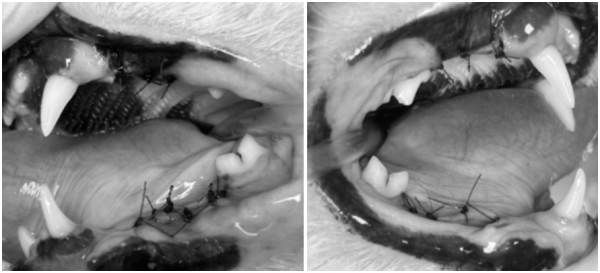

치아흡수성병변이 확인된 치아는

이미 손상된 치질이 회복되지 않기 때문에

발치를 통해 통증의 원인을 제거해야 합니다.

수술 후에는 남은 치근 여부를 확인한 뒤

치료 부위를 세밀하게 정리하여 감염 위험을 최소화합니다.